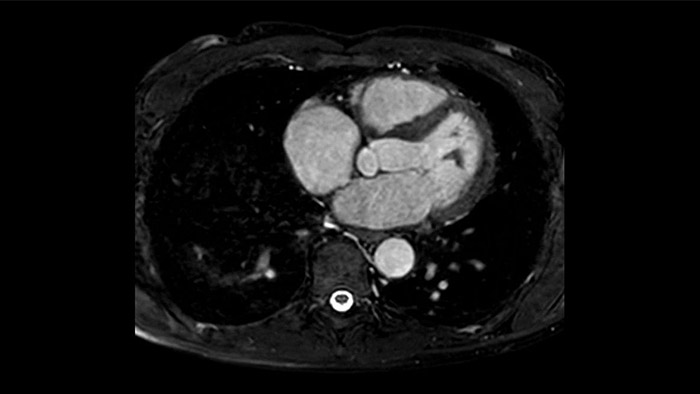

Diagnostic and prognostic utility of cardiac MR is increasing. Assess the anatomy and function of the heart using cine acquisitions, acquire information about perfusion and viability of the cardiac tissue, visualise potential edema with black blood sequence, access and even quantify tissue characterisation with CardiacQuant.

IntelliSpace Portal offers a Comprehensive Cardiac MRI Suite, providing dedicated workflows for functional analysis, viability, LGE, cardiac mapping assessment and RV/LV functional analysis in less than 5 min. per case1.